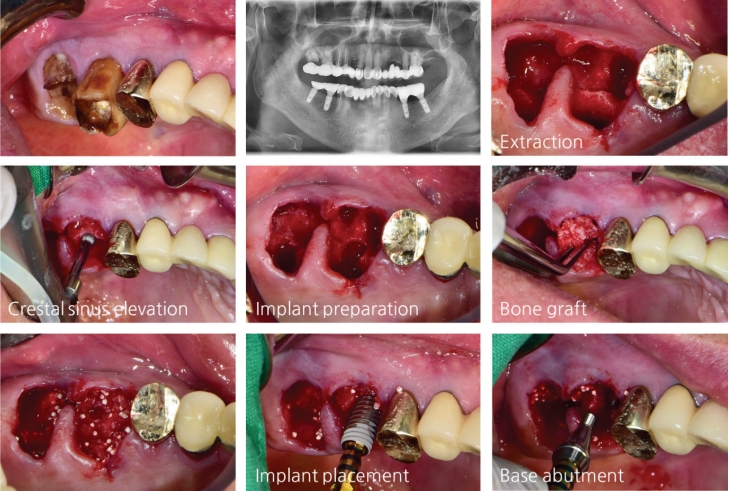

B. Multi-unit case (Fig. 6)

#16, 17 부위의 발치 후 즉시 식립과 골이식을 동반한 상악동 거상 술을 동시에 시행하였다. 임플란트 식립 후 base abutment를 40N의 torque로 연결하였다.

6주 뒤 Intraoral scanner (Omnicam, 덴츠플라이 시로나)로 임플란트 인상을 채득하고 하이니스 임시보철물로 temporary loading 시행했다. 한 달 뒤 최종 지르코니아 보철물로 final loading을 시행했다.